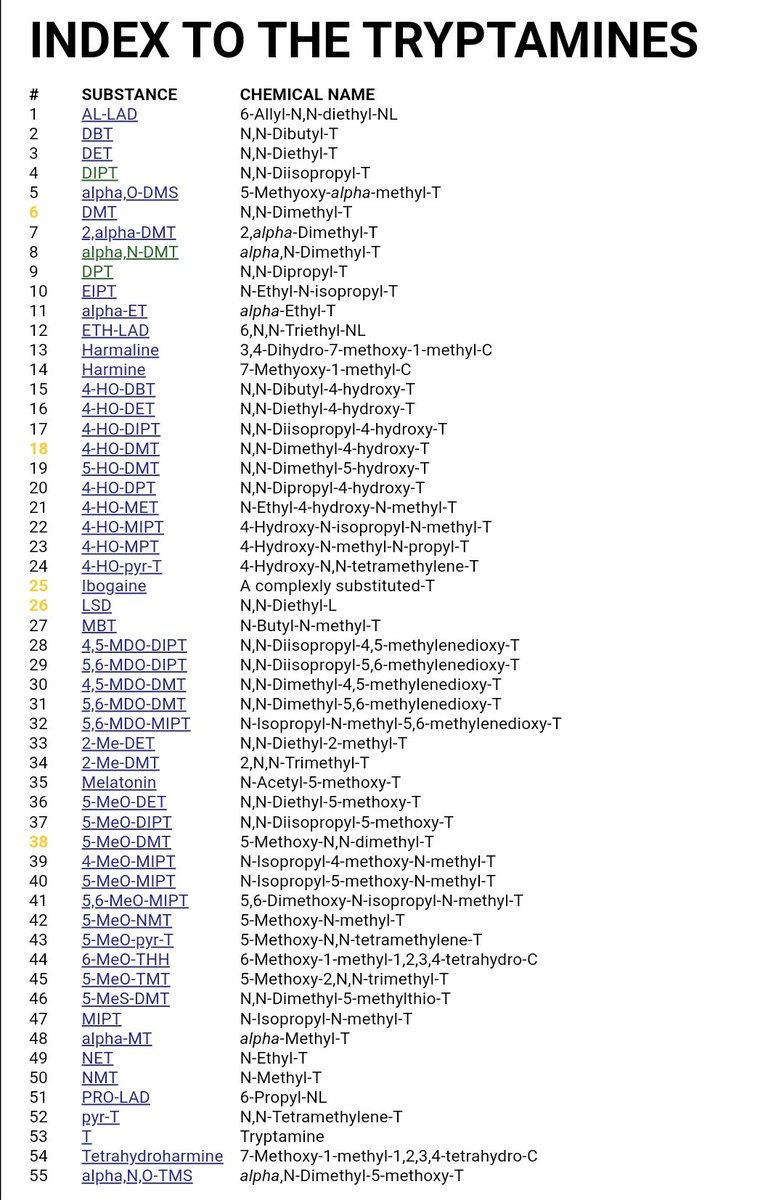

首先,从定义上讲,“反解离(anti-dissociative)”并不是一个标准的医学术语或者广泛认同的药理学分类。在正规资料,比如医学文献、维基百科、精神药理学教科书中,目前并没有“反解离药物”这个正式概念。

看上去像是为了描述某类特定效应而创造的术语(可能是nmda受体活性增强),用来对抗因NMDA受体拮抗剂(比如氯胺酮、DXM、PCP等)引发的解离体验(dissociation)。

那么更常见的是将其归入认知增强剂(cognitive enhancers),特别是改善认知连接性(connectivity)和现实感知(reality testing)的类型。